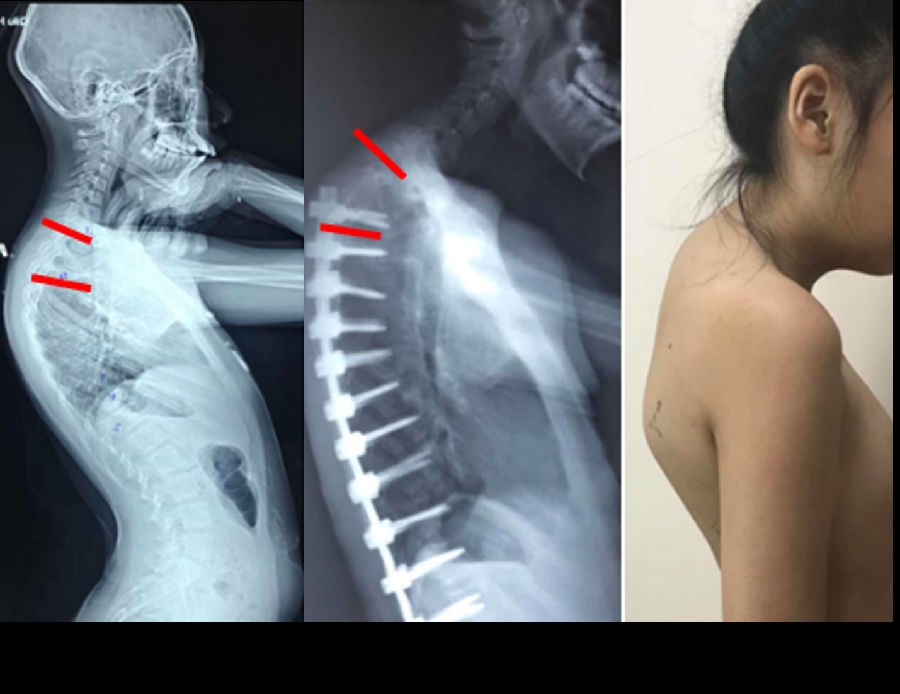

图7 术前-术后1个月-术后1个月外观

图6 长节段融合固定上固定椎(UIV)选择在胸10-12胸腰椎交界区是PJK的风险因素之一

(2)上固定椎在交界区或存在交界性后凸

(3)上固定椎位于T1-3